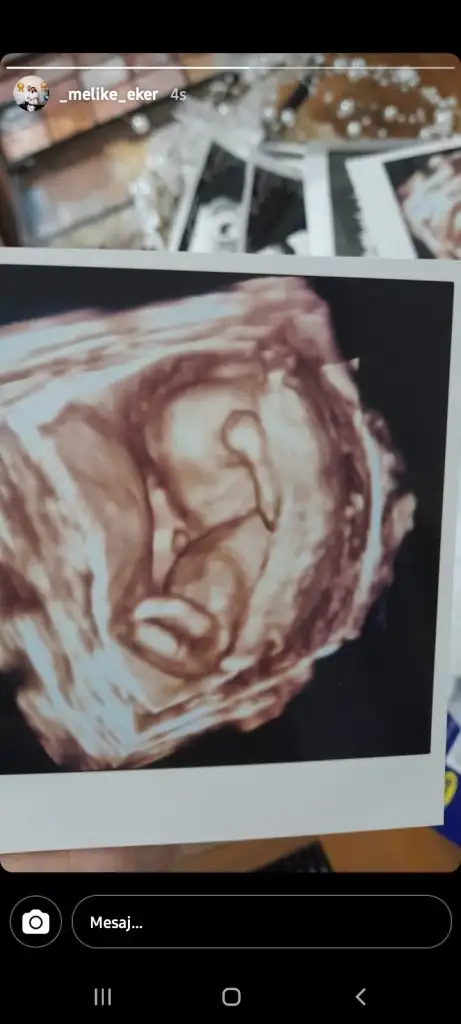

Kacinci haftadasiniz? Bana da 11+3 ve 15+3te kız dendi ama yanılma var mıdır diye korkmuyor değilimAyyy ben dün öğrendim. Gerçekten de kııııızzzzz

15+3de öğrendim bendeKacinci haftadasiniz? Bana da 11+3 ve 15+3te kız dendi ama yanılma var mıdır diye korkmuyor değilim

Bu yanilma olan kişiler çok nadir ama insanın başına gelmez diye birsey yok15+3de öğrendim bendebu haftadan sonra değişme ihtimali yok dimi tahmininizin dedim. Yok hayır bacak arasını çok net gördüm boş dedi

Az önce doktordan geldim devlet olduğu için eski hastaları unutuyor doktor cinsiyeti nedir dedim kız dedi değişir mi dedim kimse için kolay kolay söylemek ama kesin söylüyorum kız değişmez dedi15+3de öğrendim bendebu haftadan sonra değişme ihtimali yok dimi tahmininizin dedim. Yok hayır bacak arasını çok net gördüm boş dedi

Yiaaa minnoşum. Bende değişmez umarım diyordumAz önce doktordan geldim devlet olduğu için eski hastaları unutuyor doktor cinsiyeti nedir dedim kız dedi değişir mi dedim kimse için kolay kolay söylemek ama kesin söylüyorum kız değişmez dedi